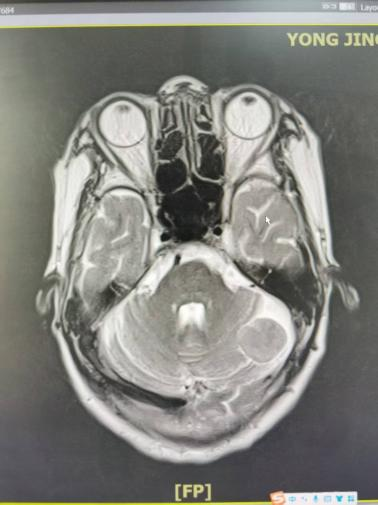

病例三:表皮样囊肿——掌握影像“金标准”

一例外伤患者,颅脑磁共振检查,显示患者小脑半球存在一特征性占位,在DWI序列上呈显著高信号——这一影像学表现正是表皮样囊肿(又称“珍珠瘤”)

表皮样囊肿虽为良性,但其沿蛛网膜下腔“见缝就长”的生长方式极具特点。通过对此病例的深入分析,孔令超对这一疾病的影像学“金标准”有了更深刻的认识,也进一步掌握了其与蛛网膜囊肿等相似病变的鉴别要点。这一病例的讨论,让团队对颅内囊性占位的鉴别诊断能力得到提升。